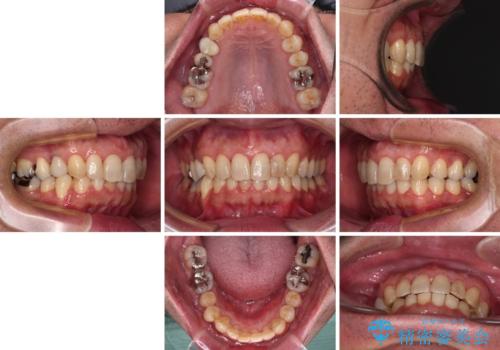

- 外に飛び出した側方の歯と、前歯のデコボコを気にして来院された患者様です。

IPR(歯と歯の間を削る)によってデコボコが解消するように設計し、インビザラインにより治療を行うこととしました。

治療途中で1年半以上通院されない時期があったため、後戻りが生じたことで治療期間が長くなってしまいました。

親知らずを抜去したことで、下顎のデコボコがきれいに解消されました。